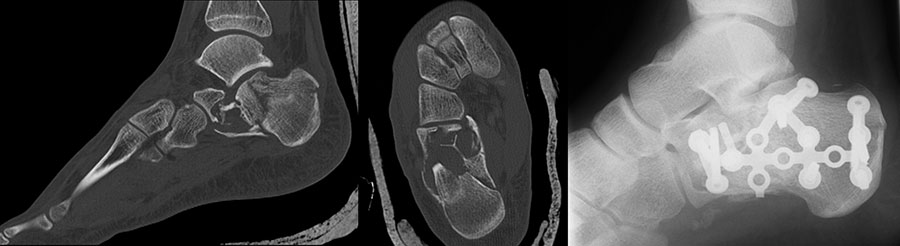

Weite Resektion

Bei der operativen Therapie maligner Neoplasien ist im Rahmen eines kurativen Therapie­ansatzes die weite Resektion zwingend erforderlich. Dabei richtet sich das jeweilige operative Vorgehen mit der nachfolgenden Rekonstruktion nach der Lokalisation des Tumors. Bei Läsionen im Bereich der distalen Tibia ist eine Segmentresektion des Knochens mit möglicher Überbrückung des Defekts durch Verwendung eines Tibia-Verschiebespans oder Fibula-Autografts und gleichzeitige Arthrodese im Bereich des oberen Sprunggelenks möglich. Aufgrund der hohen Belastung in diesem Extremitätenabschnitt ist eine Doppelung der Fibula und Anlagerung zusätzlicher Beckenkammspongiosa zu diskutieren (Burgkart, 2003). Bei Neoplasien im Bereich der distalen Fibula kann mit segmentaler Resektion des betroffenen Knochenabschnitts inklusive lateralem Malleolus und Durchführung einer tibio-talaren Arthrodese mit geringgradiger Extremitätenverkürzung meist ein funktionell gutes Ergebnis erzielt werden. Ist der Knochentumor im Bereich der posterioren Talusanteile lokalisiert so kann nach Osteotomie im Bereich des Talushalses unter Verkürzung der Extremität eine tibiocalcaneare Arthrodese mit Einbeziehung des restlichen Talus im Sinne einer Blair-Arthrodese durchgeführt werden 28. Bei Tumoren im Bereich des Calcaneus, die eine weitere Resektion notwendig machen, ist entweder eine Syme-Amputation oder die isolierte Resektion des Calcaneus mit Versorgung des entstandenen Defekts durch einen myo-cutanen Lappen und Verwendung spezieller Schuhe möglich (Burgkart, 2003). Ausgeprägte Befunden, die über die Höhe des oberen Sprunggelenks hinausreichen, erfordern selten eine distale Unterschenkelamputation (Abb. 10a-e). Die früheren Amputationsschemata, die von Amputationen in der distalen Hälfte des Unterschenkels abgeraten haben, besitzen heute keine Gültigkeit mehr 29. Dem Erhalt der Länge ist nach Beachtung einer entsprechenden Radikalität der Tumorresektion höchste Priorität zu bemessen. Bei Tumorlokalisation im Bereich des Mittelfußes können nach vollständiger Entfernung des jeweiligen Knochens Rekonstruktionen unter Verwendung autologer oder allogener struktureller Transplantate ("strut grafts") zu funktionell guten Mittelfußarthro­desen führen (Abb. 11) (Burgkart, 2003). Mit Ausnahme der großen Zehe können Amputationen der Zehen meist gut kompensiert werden. Amputationen in Höhe der Grund- und Mittelglieder der Kleinzehen sind wegen der Imbalance der Muskulatur mit sekundären Fehlstellungen zu vermeiden 29.